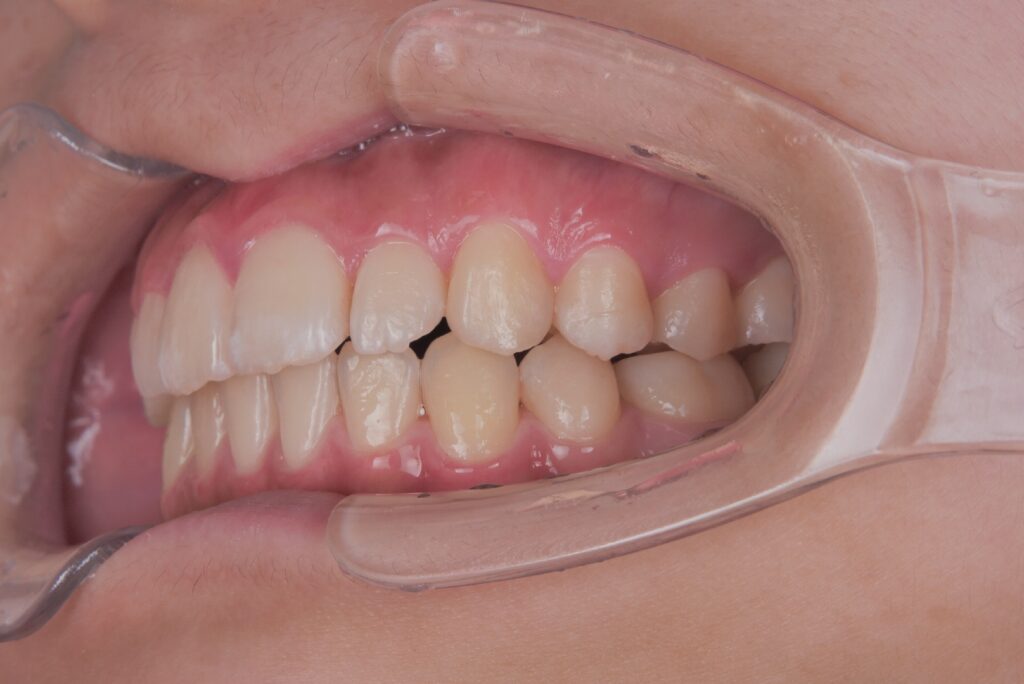

上顎の前歯が大きく突出しています

明らかに前歯の突出感が改善し、患者様はこの時点でとても喜ばれていました

矯正治療終了時 部分矯正ということもあり、短期間で矯正治療を終了することができました